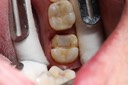

Wayne Chin #30 pre-op